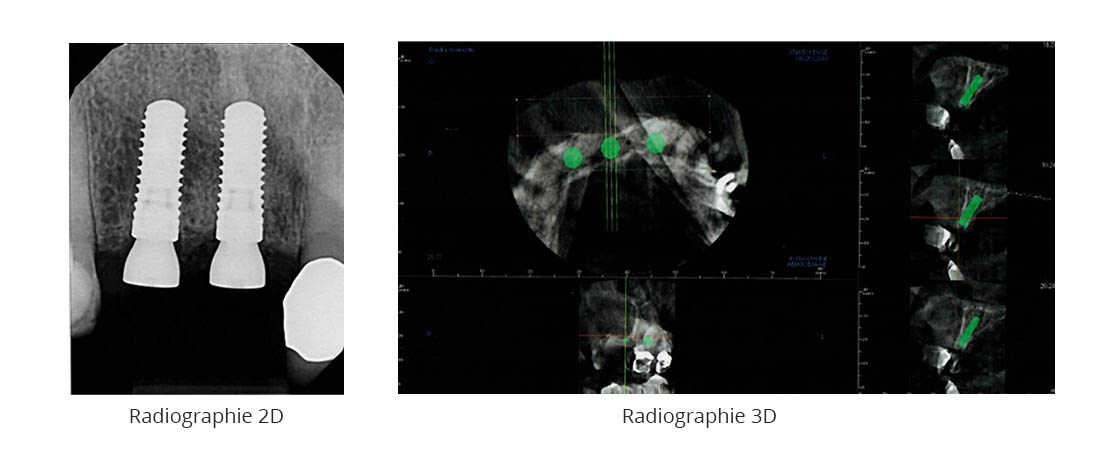

Quelques exemples

La quantité d’informations recueillies par ces radiographies est importante. Le Dr David peut y voir :

- les os de votre mâchoire ;

- votre dentition complète ;

- les chevauchements dentaires ;

- des pathologies pas toujours visibles en 2D ;

- la localisation de vos nerfs ;

- la densité de votre masse osseuse en préparation d’une chirurgie d’implants dentaires.

Pour ces raisons et d’autres encore,

la radiographie dentaire 3D est très efficace dans la planification d’une chirurgie implantaire, d’une extraction, d’une greffe osseuse et de toutes autres chirurgies de précision.